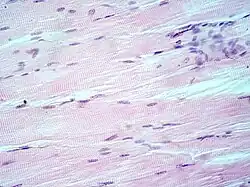

Muscle tissue, cell nuclei (blue-purple), cell body (pink)

H&E is the combination of two histological stains: hematoxylin and eosin. The hematoxylin stains cell nuclei a purplish blue, and eosin stains the extracellular matrix and cytoplasm pink, with other structures taking on different shades, hues, and combinations of these colors.[5][6] Hence a pathologist can easily differentiate between the nuclear and cytoplasmic parts of a cell, and additionally, the overall patterns of coloration from the stain show the general layout and distribution of cells and provides a general overview of a tissue sample's structure.[7] Thus, pattern recognition, both by expert humans themselves and by software that aids those experts (in digital pathology), provides histologic information.

Hematoxylin principally colors the nuclei of cells blue or dark-purple,[6][15][14] along with a few other tissues, such as keratohyalin granules and calcified material. Eosin stains the cytoplasm and some other structures including extracellular matrix such as collagen[5][7][14] in up to five shades of pink.[8] The eosinophilic (substances that are stained by eosin)[5] structures are generally composed of intracellular or extracellular proteins. The Lewy bodies and Mallory bodies are examples of eosinophilic structures. Most of the cytoplasm is eosinophilic and is rendered pink.[10][15] Red blood cells are stained intensely red.